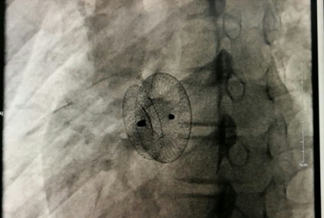

我院成功開展市屬醫(yī)院首例先心病介入封堵術(shù)?不用開刀,不會(huì)在體表留下疤痕,只需進(jìn)行局部皮膚麻醉,通過穿刺右側(cè)股靜脈插入一根幾毫米的導(dǎo)管,將封堵器送至缺損部位釋放,先天性心臟病就得到了根治。不久前,15歲的小章在我院成功接受了先天性心臟病介入封堵術(shù),他的心臟結(jié)構(gòu)和功能恢復(fù)了正常,學(xué)習(xí)和生活也得到了恢復(fù)。...